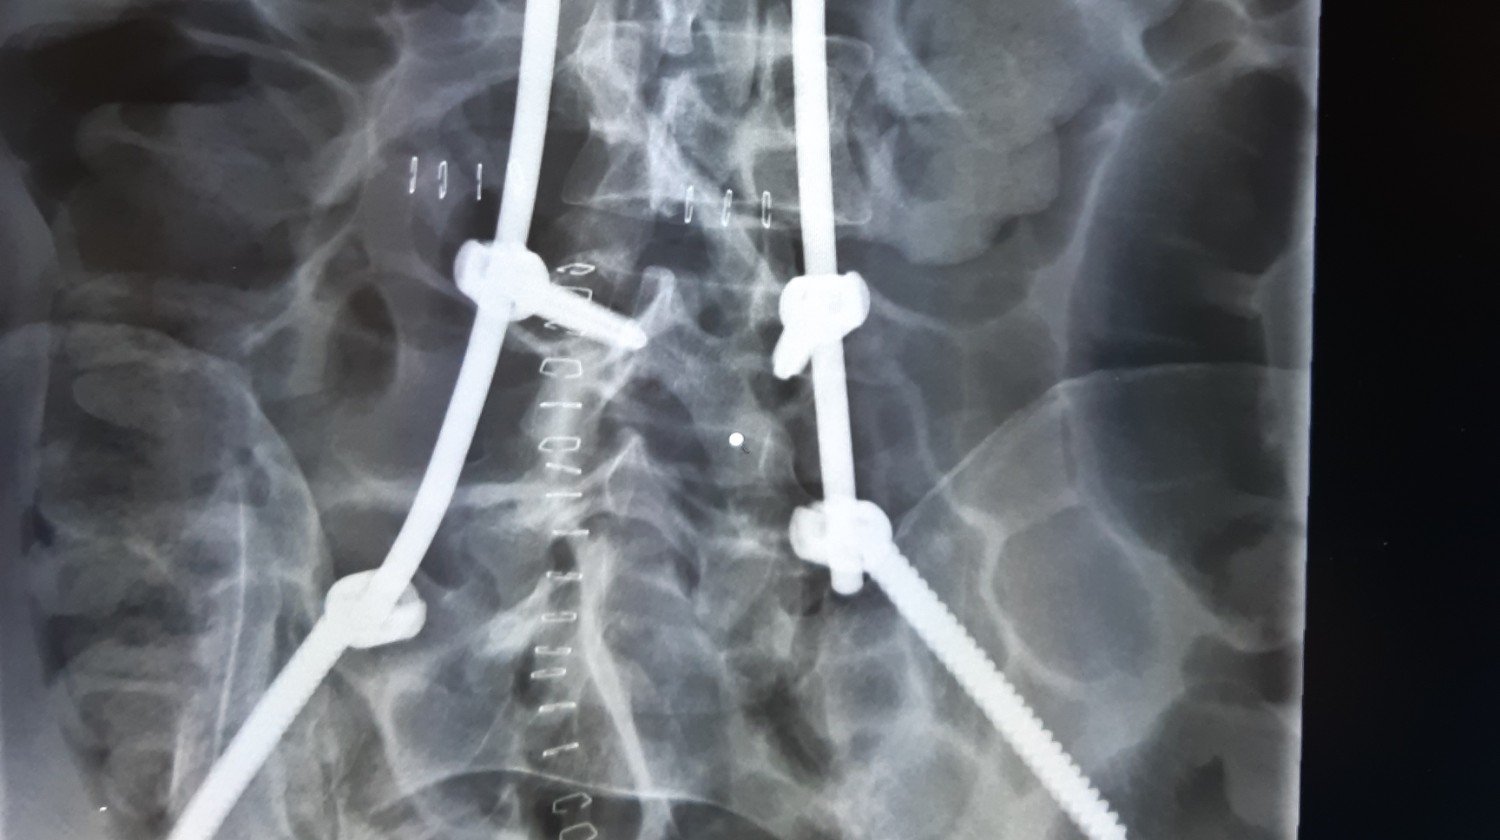

Po niedawnym wypadku moje życie zmieniło się drastycznie. Obrażenia uniemożliwiają mi normalne funkcjonowanie i powrót do zdrowia. Proszę o wsparcie finansowe na rehabilitację, która jest kluczowa dla mojego powrotu do sprawności. Każda wpłata będzie ogromną pomocą w mojej drodze do zdrowia. Dziękuję za każdą okazaną pomoc i wsparcie.